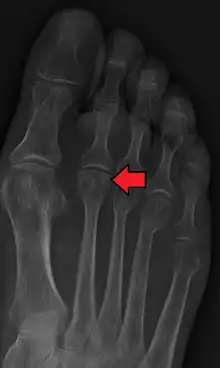

| Freiberg disease as seen on plain film | |

Freiberg disease, also known as a Freiberg infraction, is a form of avascular necrosis in the metatarsal bone of the foot. It generally develops in the second metatarsal, but can occur in any metatarsal. Physical stress causes multiple tiny fractures where the middle of the metatarsal meets the growth plate. These fractures impair blood flow to the end of the metatarsal resulting in the death of bone cells (osteonecrosis). It is an uncommon condition, occurring most often in young women, athletes, and those with abnormally long metatarsals. Approximately 80% of those diagnosed are women.[1]